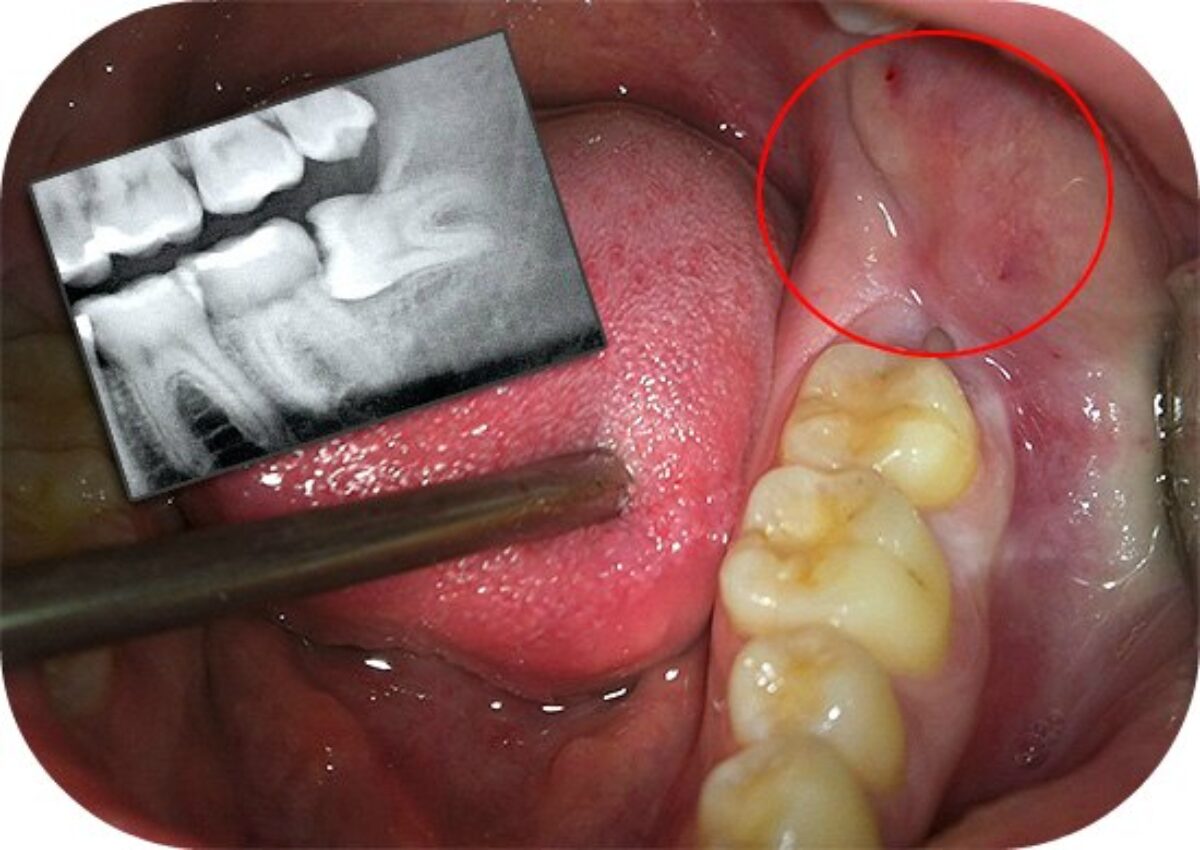

| Перикороніт | Запалення, викликане частково прорізаним зубом мудрості. |

| Карієс | Закрутили карусель? Недоступність мудрості може сприяти розвитку карієсу. |